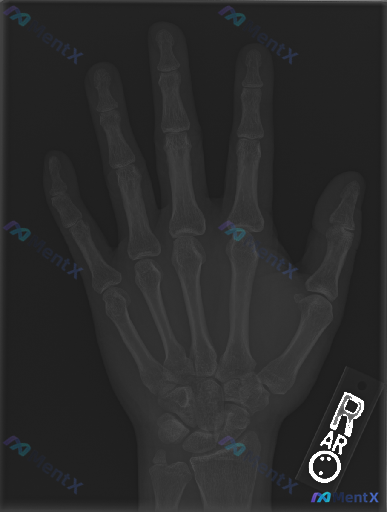

整理到一个临床与影像结合的手部病例资料,想和大家讨论一下思路: --- 影像资料:右侧手部正位X光片 影像学观察: - 骨骼:各掌骨、指骨、腕骨骨皮质连续,未见明确骨折线、成角或阶梯状改变;骨小梁排列规律,未见局部密度异常减低或硬化区;第一掌骨基底部、第五掌骨颈等特定部位也未见典型骨折表现。 - 关...